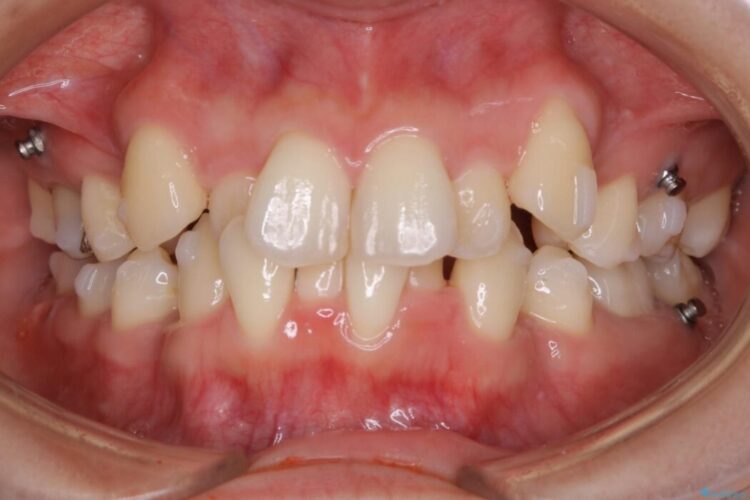

ガタガタな歯並びをなおしたいとのことで来院されました。

左右の奥歯が前方に寄っていることにより八重歯の発生や重度の叢生に繋がっていました。

笑った時に見えるガタついていた見栄えが改善されて歯列弓もきれいな形に整い、患者様にはご満足いただけました。